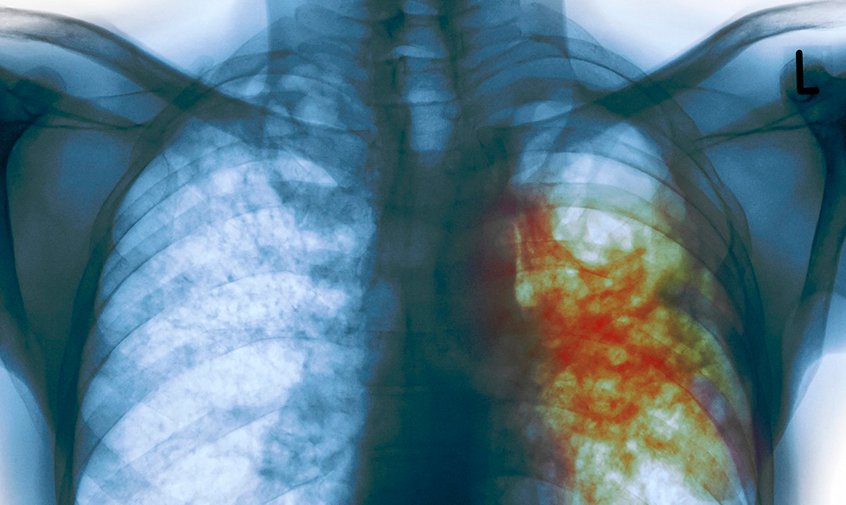

Туберкулез — широко распространенное в мире инфекционное заболевание человека и животных, вызываемое палочками Коха. Туберкулез обычно поражает легкие, реже затрагивает другие органы и системы. Инфекция передается воздушно-капельным путем при разговоре, кашле и чихании больного. Чаще всего после инфицирования микобактериями заболевание протекает в бессимптомной, скрытой форме, но примерно один из десяти случаев скрытой инфекции, в конце концов, переходит в активную форму.